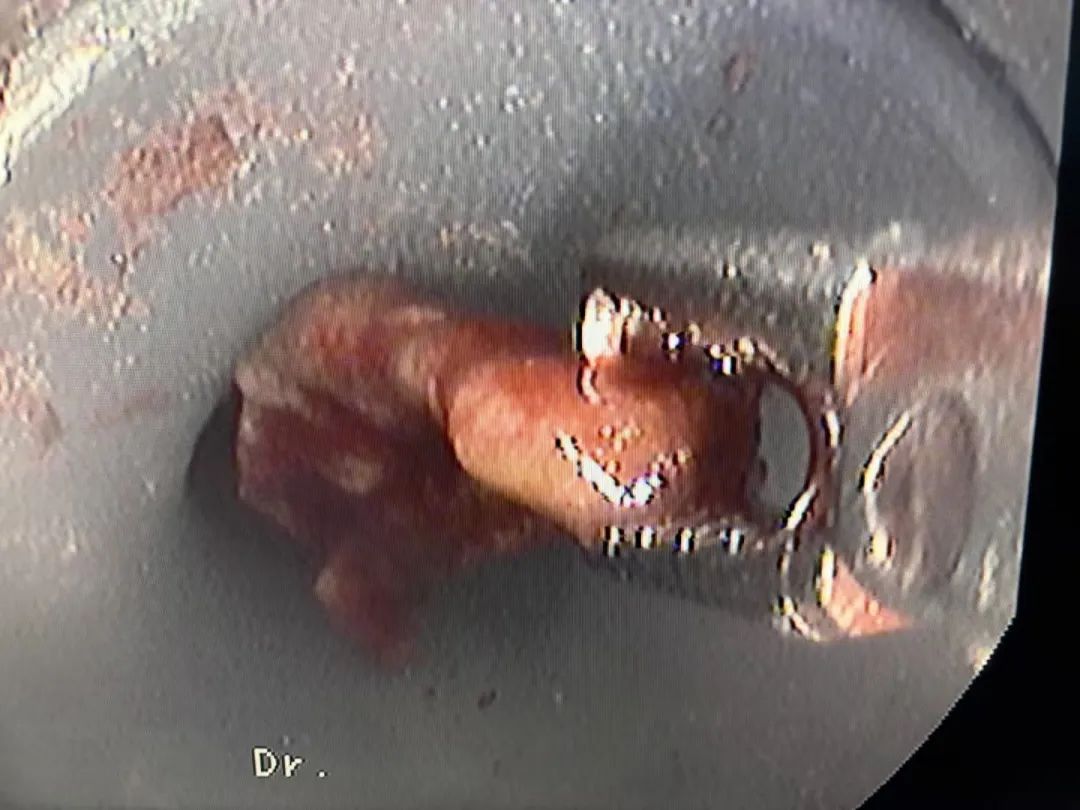

在确定了治疗方案后,东方总院呼吸与危重症学科医疗中心杨传留院长亲自上阵,运用气管镜技术为王大爷进行手术,无影灯下展开了一场惊心动魄的“气道寻宝”。手术过程中,杨院长凭借精湛的医术和丰富的经验,精准地定位到了被肉芽包裹的鱼骨,小心翼翼的将鱼骨与周围组织逐步分离,最终将这块呈倒钩状、长达2厘米的鱼骨完整取出。术后,王大爷的咳嗽和咳痰症状迅速得到了缓解,他的身体也逐渐恢复了健康。

▲东方呼吸与危重症医学科气管镜下取出异物